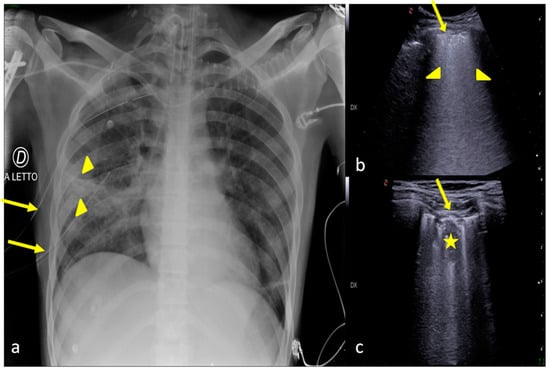

2.6. Pulmonary Contusion

3. Confirming or Excluding Pneumothorax and Monitoring its Evolution

4. Checking and Monitoring the Devices